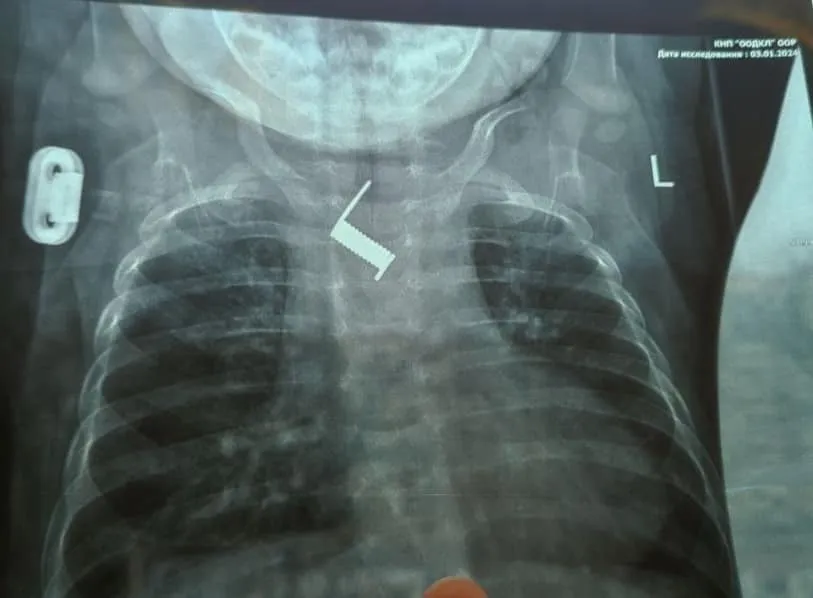

В Одеській обласній дитячій клінічній лікарні медики врятували життя немовляті, яке проковтнуло пружину. Лікарі витягли сторонній предмет із стравоходу дитини.

Пружину з стравоходу шестимісячної дитини витягли за допомогою ендоскопії у відділенні інструментальних методів дослідження та лікування. Лікарі розповіли, що дитину амбулаторно лікували у районній лікарні від бронхіту та пневмонії протягом двох тижнів. Після того, як стан маленького пацієнта не покращувався, його госпіталізували до обласної дитячої лікарні.

Медики зазначили, що за два тижні пружина майже вросла у стінку стравоходу немовляти. При потрапланні у стаціонар лікарні було виконано оглядову рентгенограму, за результатами якої було виявлено сторонній предмет у тілі дитини, а саме пружинку від шпильки для волосся.

"Знаходилось стороннє тіло на рівні середньої третини стравоходу, поряд з дугою аорти. Стороннє тіло було видалено ендоскопічно,що позбавило дитину від важкого хірургічного втручання та ризиків для життя", – розповіли медики.